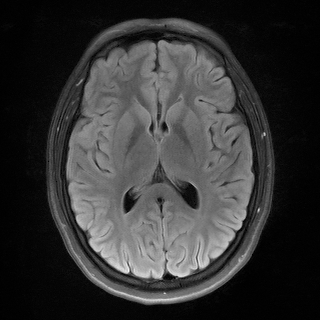

MRI We evaluate on the fastMRI brain validation set using the single-coil accelerated acquisition procedure from Zbontar et al. (2018) with acceleration factors and . The problem is formulated as , where is a binary mask and the discrete Fourier transform, and . Quantitative results are reported in Table 2 and visuals in Figure 7. The proposed RAM model outperforms all baselines.

We provide in Figure 7 visual results for MRI reconstructions on acceleration factors 4 and 8 respectively.

| uDPIR tied | RAM | Ground-truth | ||

| acc. factor 4 | ![]() |

![]() |

| 0.863 | 0.868 | SSIM | ||

| acc. factor 8 | ![]() |

| 0.831 | 0.840 | SSIM |